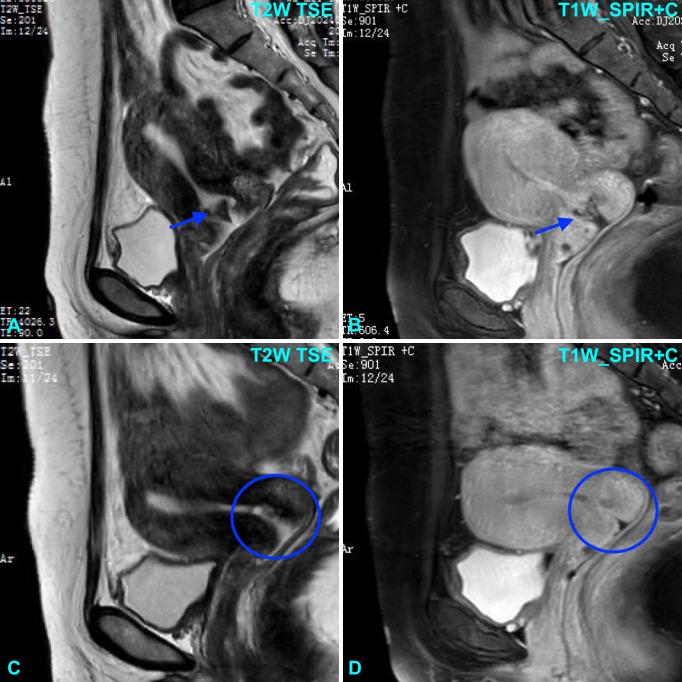

绒毛膜癌属于一组高度侵袭性的恶性妊娠滋养细胞肿瘤。绒毛膜癌根据起源可分为两种类型:一种是在正常或异常妊娠后发生的妊娠型,另一种是非妊娠型,由生殖细胞或体细胞癌的滋养细胞分化产生。原发性宫颈绒毛膜癌罕见;在近期无妊娠史的女性中,它常被误诊为其他宫颈癌,而其他宫颈癌通常需要手术治疗。在此,我们报告一例47岁女性原发性宫颈绒毛膜癌病例,该患者出现不规则阴道出血5个月,其最后一次妊娠是在6年前。她最初被误诊为宫颈鳞状细胞癌。进一步评估,包括血清人绒毛膜促性腺激素(hCG)检测和全面的病理评估,确诊为妊娠性绒毛膜癌。免疫组化显示hCG染色阳性,p40和p63染色阴性,Ki-67指数高(60%)。宫颈绒毛膜癌不常见,且与鳞状细胞癌具有相似的形态学特征。全身化疗后,hCG水平显著下降,病变消退,反应良好。该病例突出了原发性宫颈妊娠性绒毛膜癌相关的诊断陷阱以及临床关联的重要性,尤其是在近期无妊娠史的患者中。